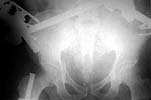

To recap: Middle aged male patient on whom a heavy log fell and sustained injury. Had pelvic ring disruption with fracture femur. Ext fix of pelvis and interlocking nailing of femur done. Developed compartment syndrome thigh and had fasciotomy. Went on to rhabdomyolysis and ARDS. Managed with ventillation and alkalinising. Fasciotomy wound later skin grafted.

Now what I have not told so far: At about three weeks after the injury when patient had recovered from the problems described above developed acalculous cholecystitis. As he was being prepared for surgery he suddenely collapsed and went into shock. Required resuscitation and inotropic support. After vital signs were stable he was taken up for laparoscopic cholecystectomy. On introducing the scope it was found that there was a gangrenous gall bladder with lots of inflammation all around. It was converted to an open cholecystectomy. Ventillated post op. Patient's ext fix on pelvis was removed after six weeks and ambulated with walker. Had developed a deep sacral pressure sore. Discharged with home care of pressure sore and ambulation with support. Now at about three weeks the femur is uniting, pelvis stable and the pressure sore healing. Patient changed to axillary crutches from walker.

My question to the list: How often do you see acalculous cholecystitis following pelvic fracture? Any other comments?? Laparoscopic picture of gall bladder and present x-rays attached.